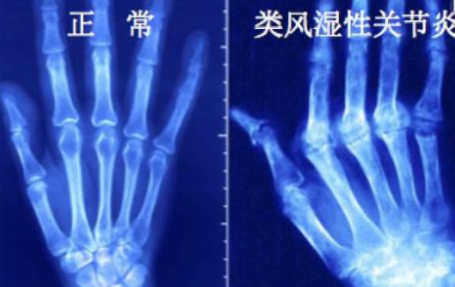

风湿病可以引起类风湿,类风湿这个疾病是一种常见的风湿病,但并不是所有的风湿病会引起类风湿。风湿病是一大类疾病的统称,凡是影响到关节肌肉及其周围组织,同时可以出现一些其他系统受累,化验有特异性的...[详细]